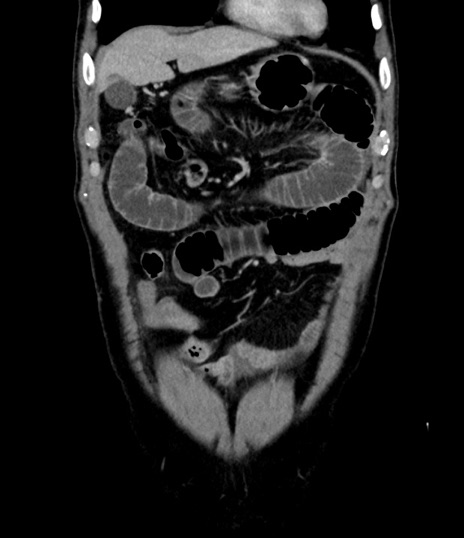

症例8(冠状断像)

【症例】 60歳代男性

【主訴】 黒色吐物

【現病歴】 4日前から嘔気自覚、2日前の朝食後にも嘔気あり、自分で手で嘔吐反射起こし嘔吐したところ血が混ざっていたため受診。

【既往歴】 5年前汎発性腹膜炎を伴う急性虫垂炎で手術、高血圧、前立腺肥大症、高脂血症

【身体所見】 腹部正中に手術癩痕あり 腹部平坦・軟圧痛なし膨満感あり

【データ】WBC 8400、CRP 4.54